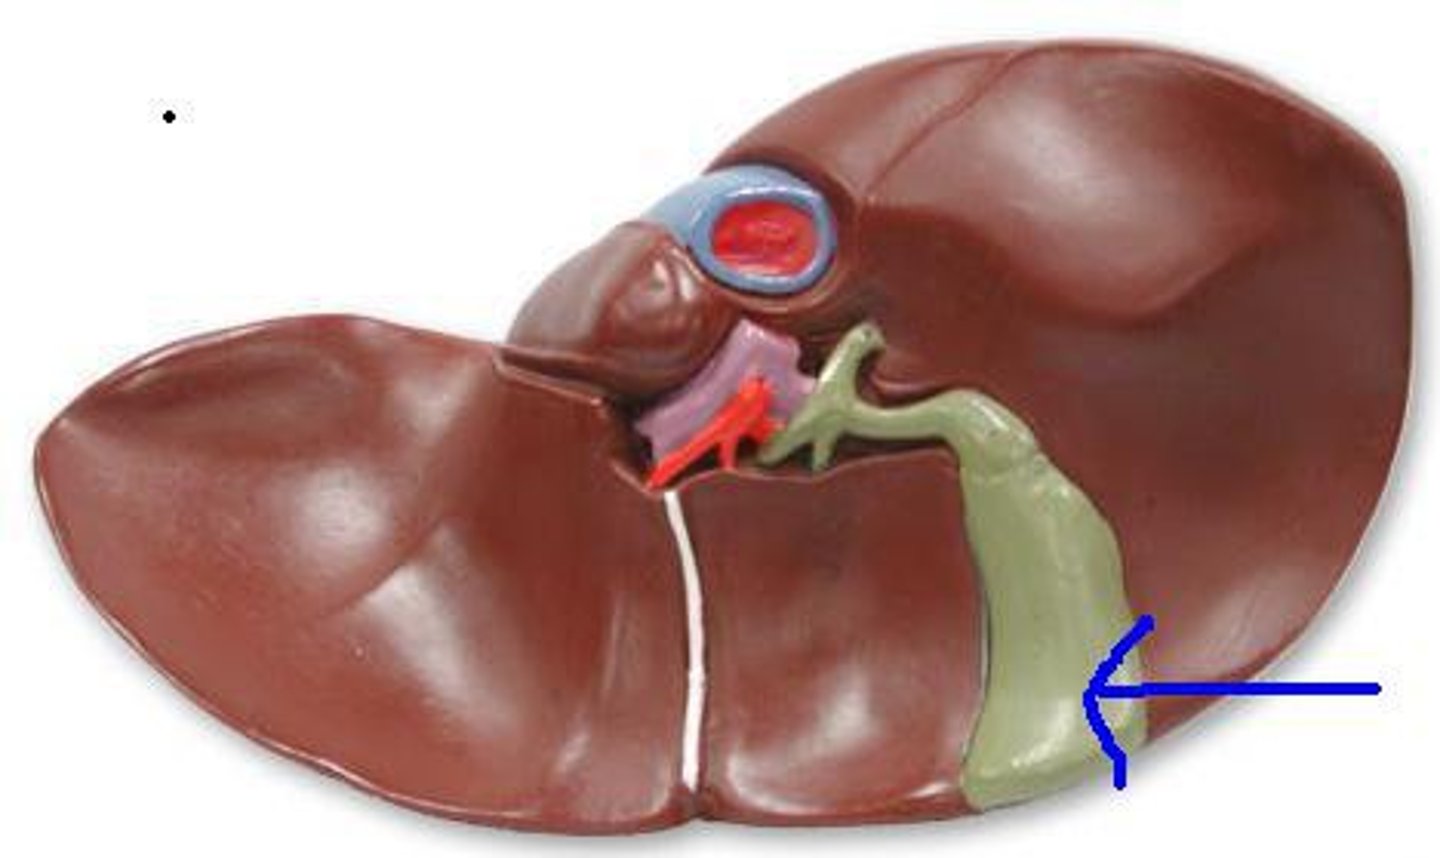

liver

cystic duct

common hepatic duct

Gallbladder

portal vein

pancreas

organ

pancreatic duct

common bile duct

spleen

hepatopancreatic sphicter / duodenal papilla